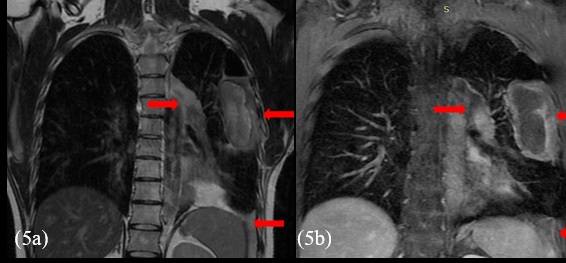

A 28-year-old male patient presented with onset of pain on his left hemithorax and progressive fatigue, in September, 2020. He had no previous comorbidities. An investigative MRI (magnetic resonance imaging) scan showed a large and heterogeneous mass on his left hemithorax with partial lung atelectasis, inferior displacement of diaphragm, mediastinal shift to the right and small pleural effusion (Figures 1a, 1b and 1c). The tumor was in contact with the inferior esophagus and the descending aorta. The thoracic wall (muscle and ribs) was not compromised. These findings suggested, possibly, a mass of pleural origin. An initial core-needle biopsy was performed in October, 2020 to clarify the diagnosis.

Before opting for some new agent, empirically, a next generation sequencing analysis was performed on the primary tumor tissue, to guide the subsequent therapy. An amazing pathogenic HMBOX1-ALK gene fusion was identified. Thus, we decide to continue his treatment by administering crizotinib, a tyrosine -kinase inhibitor (TKI) approved in Brazil for usage in lung cancer with ALK translocation. At the beginning of oral therapy, he manifested nausea grade 2, vomit grade 1 and diarrhea grade 2, according to WHO (World Healthy Organization) profile toxicity; all of these symptoms were manageable with regular antiemetic drugs and loperamide. Approximately, one month after the beginning of the new treatment, he reported reduction of chest pain and cough, as well as diminishing of tiredness and dyspnea, which were present only with great effort. The evaluation images with 45 days of crizotinib therapy showed reduction of all the lesions with appearance of necrotic/hemorrhagic areas (Figures 5a and 5b).